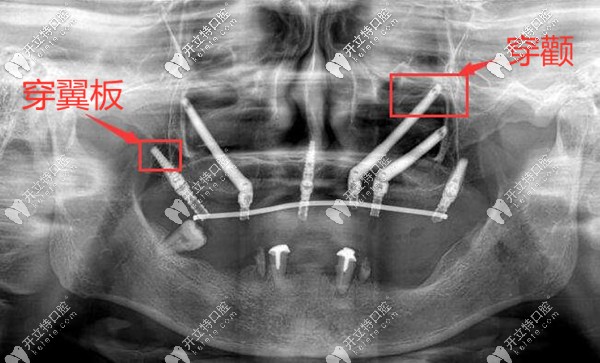

上頜牙槽骨大量缺失,穿顴穿翼板種植案例▼

深圳正夫口腔熊靖宇穿顴穿翼板種植牙案例